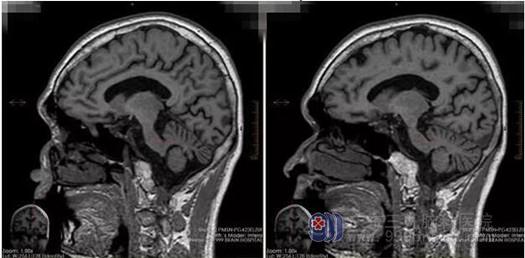

主管医生匡祖颖指出,李先生这种情况为酒精中毒性脑病,同时伴有小脑变性,是慢性酒精中毒的累及神经系统的特征性改变,临床表现为精神障碍,认知能力下降,躯干及四肢的共济失调、眼球震颤、言语缓慢,部分患者合并周围神经损害。长期大量饮酒,出现精神症状、认知功能下降及小脑性共济失调,影像学提示全脑及小脑萎缩为其诊断要点。

神经内一科王展航主任医师表示,乙醇作为一种脂溶性物质,对脑组织有极强的亲和力,长期持续大量饮酒会损伤神经系统,造成胃肠功能损害,进而减低机体摄取维生素的能力,导致维生素B缺乏、糖代谢受阻、焦磷酸硫胺素减少、神经功能物质缺乏,最终表现为中枢神经、周围神经脱髓鞘和轴索的变性。